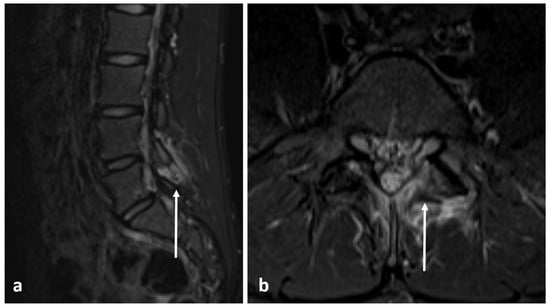

| Aneurysmal bone cyst | Expansile lytic lesion with internal bone septations. | Fluid—fluid levels within the cysts, high T1 signal within layering fluid content due to haemorrhage. |